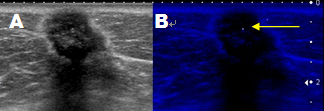

乳線悪性腫瘤の超音波像

Aが通常像、Bがマイクロピュア像

小さな微小石灰化が描出されている。

乳線悪性腫瘤のエラストグラフィー像

周辺組織に比べて病変部は高い弾性を呈示している。

乳線悪性腫瘤の水平面の超音波像

腫瘤と周囲組織の境界は不明瞭で周囲を巻き込んで横方向に伸展している。